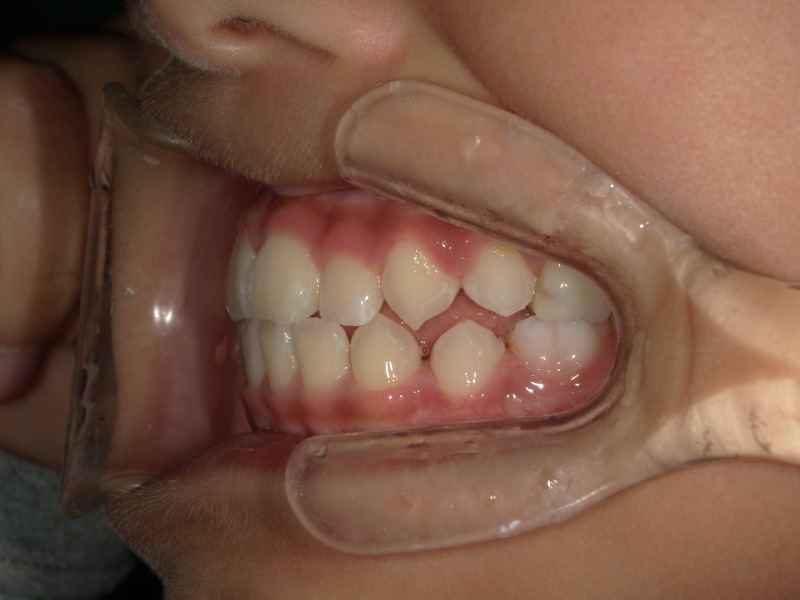

最初の頃は上下の歯と歯がぴったりで噛んでいましたが、上の顎の写真の時と同じ日の噛み合わせ写真です。

まだ生えてる途中ですが以前より上下の差があります。

とても綺麗に噛み合っています!

いつも、鼻呼吸で舌をいい位置に置く、というのを続けてくれていると歯と歯もいい位置で噛んでいきます。